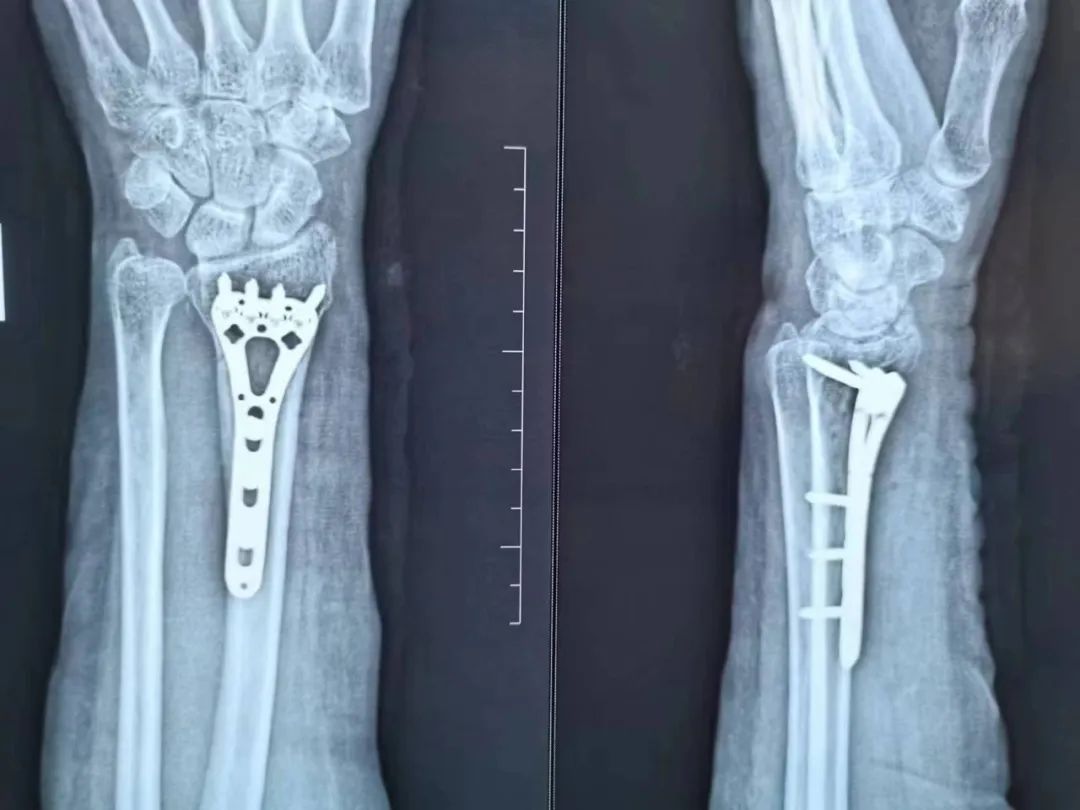

骨外科主任程广东医师亲自接诊,在仔细询问了顾奶奶的病史后,经CT及相关辅助检查诊断为“1.双侧桡骨远端骨折伴腕关节脱位 2.右侧第一掌骨骨折”。根据顾奶奶的病情及身体状况为顾奶奶量身制定手术方案,建议顾奶奶做两次手术来解决“双腕部骨折”问题。

累及关节面的粉碎性骨折、开放性骨折、保守治疗效果欠佳者就需要进行手术治疗。就是通过做手术在直视下把骨头断的地方对好,然后用钢板、螺钉或者克氏针固定住,维持骨断端稳定不移位,待骨断端长在一起就痊愈了。

这种直视下复位的方法,骨折复位程度更好,很多累及关节的桡骨远端骨折患者,强求保守治疗,手法复位很难完全恢复关节面的平整,关节面最后如同不平整的地面一样愈合后,活动的时候容易磕磕碰碰,关节就容易痛,导致创伤性关节炎。并且通过内固定物直接固定骨断端的方式,也不容易再次移位,术后可以在医师指导下早期行腕关节康复锻炼,从而较大程度的恢复腕关节功能。